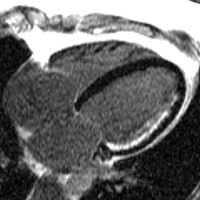

Heart function using cine imaging

Images of the heart may be acquired in real-time with CMR, but the image quality is limited. Instead most sequences use ECG gating to acquire images at each stage of the cardiac cycle over several heart beats. This technique forms the basis of functional assessment by CMR. Blood typically appears bright in these sequences due to the contrast properties of blood and its rapid flow. The technique can discriminate very well between blood and myocardium. The current technique typically used for this is called balanced steady state free precession (bSSFP), implemented as TrueFISP, b-FFE or Fiesta, depending on scanner manufacturer.

A 4 chamber view of the heart using SSFP cine imaging. Compare the image orientation (4 chamber) with the short axis view of the movie above